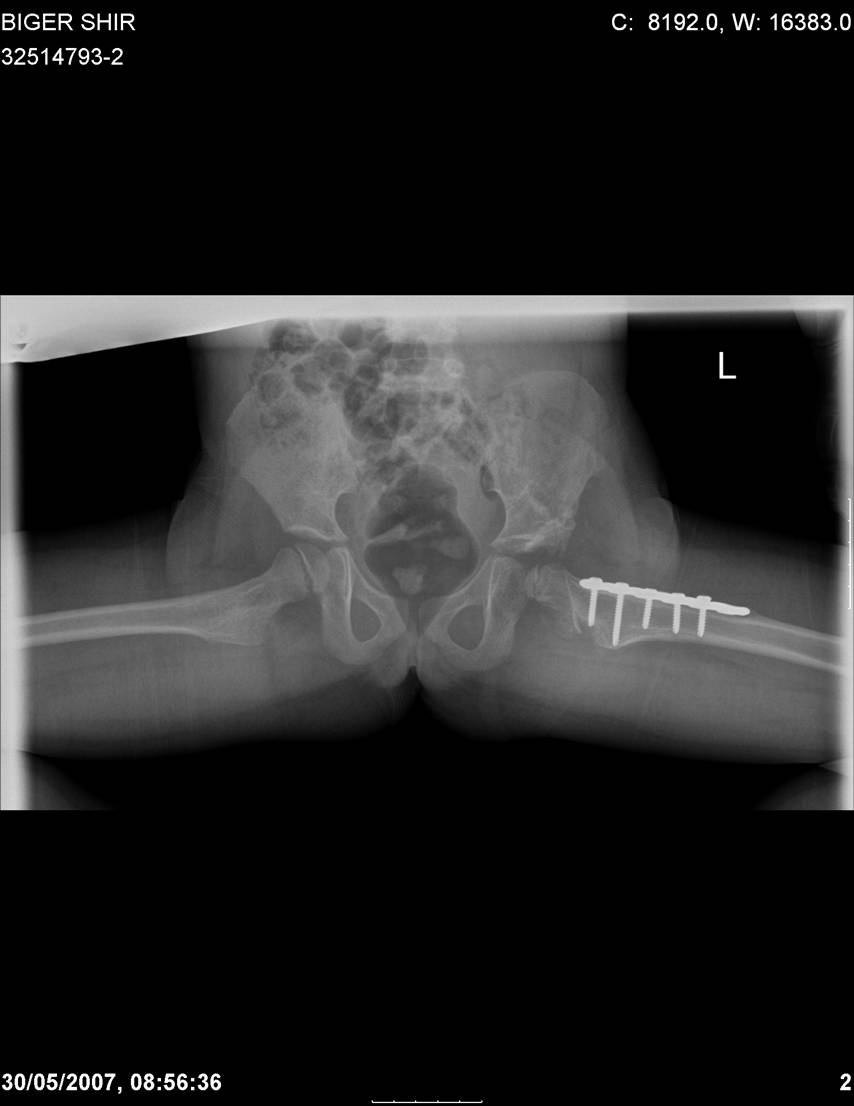

Здравствуйте, уважаемые коллеги.Обратилась девочка 6-ти лет из жалобами на боль в левом т/б суставе,хромоту Из анамнеза : ребенок лечился с рождения по поводу врожденного вывиха бедер. В возрасте 3- х лет в одной из клиник была выполнена остеотомия таза по Пембертону и варизирующая остеотомия бедра слева, справа - остеотомия таза по Солтеру и остеотомия бедра. Посоветуйте тактику лечения. С уважением Ihor

Smotritsya parshivo konechno(pseudoacetabulum,partial AVN), no v6 let ya by popytalsya ispravit chto moghno:shortening (ne boyatsya ubrat bolshoi fragment),derotation(30 gradusov ne bolshe)+pelvic osteotomy in true acetabuluam area.Obyazatelno takghe open reduction with wide capsular exposure.

Navernoe Dega

Chto by ne byt goloslovnym posilau vam svoi sluchai gde sdelal vse chto napisal vyshe

Уважаемой Ihor! Следует дообследовать ребенка, проведя РКТ или МРТ. Необходимо установить взаимоотношение головки бедренной кости и вертлужной впадины слева, оценить угол антеторсии и истинный ШДУ. Далее решать вопрос об оперативном лечении. Скорее всего показана деторсионно-варизирующая остеотомия в межвертельной области левого бедра и остеотомия таза типа Солтера (хотя ацетабулярный индекс великоват, т.е. более 30-35 градусов). Справа следует понаблюдать и периодически проводить курсы ФТО и ЛФК. Если Вы не имеете опыта реконструктивной хирургии ТБС у детей, то лучше отправить пациента к детским ортопедам. АИФ